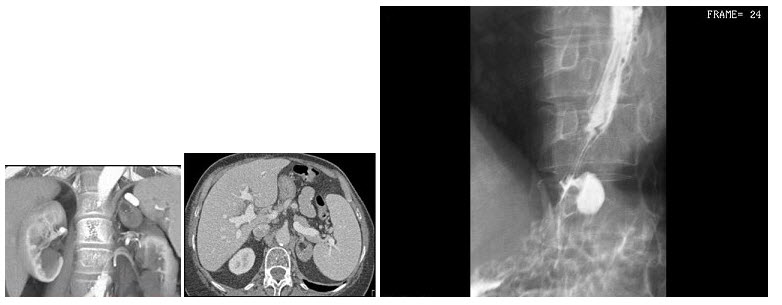

- 单项选择题女,68岁,发现高血压病30年,有痔疮史。04年12月6日大便潜血(+++),结合图像,最可能的诊断为()

- B